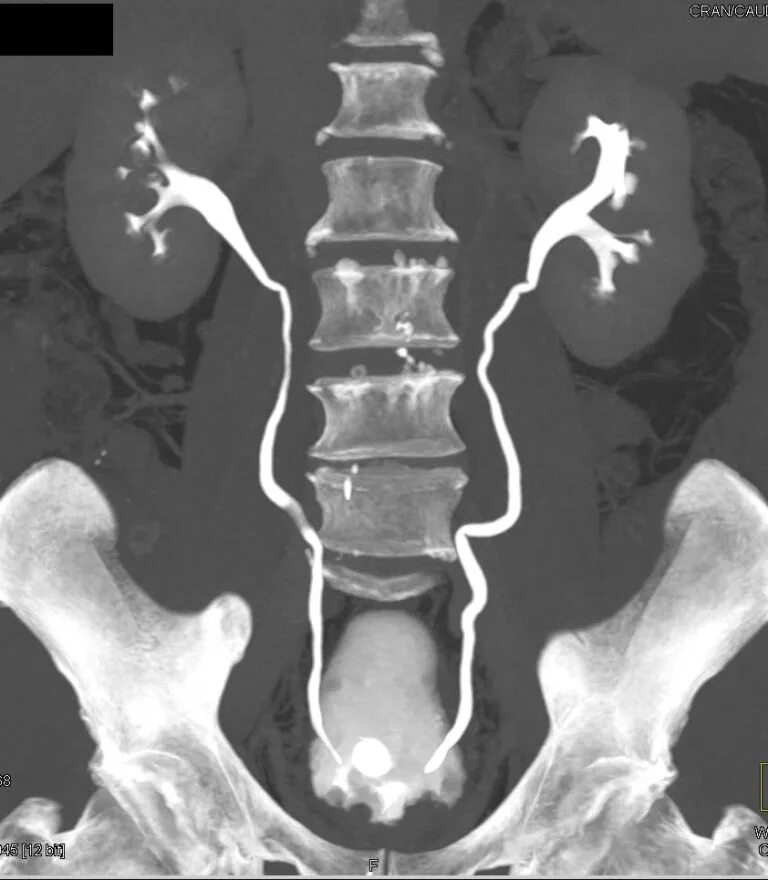

Где сделать урографию